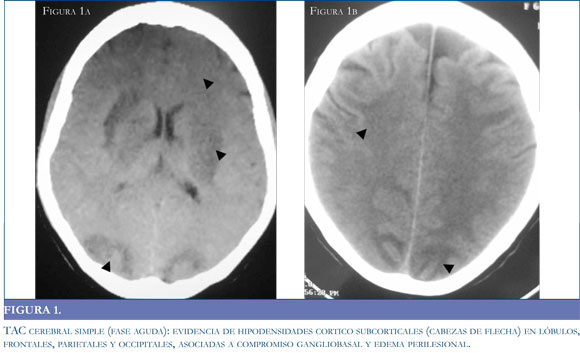

La resonancia magnética (RM) es el estándar de oro para el diagnóstico de la entidad3, (16,34) pues permite observar con claridad el compromiso de territorios vasculares. En las secuencias de T1 se observan hipointensidades con la misma localización descrita para las imágenes tomográficas, que se transforman en hiperintensidades en las secuencias de T2 (Figura 3a). Habitualmente la secuencia FLAIR (Fluid Attenuated Inversion Recovery) y las imágenes de difusión (DW) pueden ayudar a diferenciar entre el edema vasogénico reversible y el edema isquémico/citotóxico irreversible,9 al detectar la difusión intra y extracelular de moléculas de agua; el edema citotóxico disminuye la difusión de moléculas hidrosolubles mostrando una señal hiperintensa del territorio vascular afectado, en tanto que el edema vasogénico se caracteriza por un incremento relativo en la difusión de agua generando una señal iso y en menor grado hipointensa en relación al parénquima normal (24) (Figura 3 b).